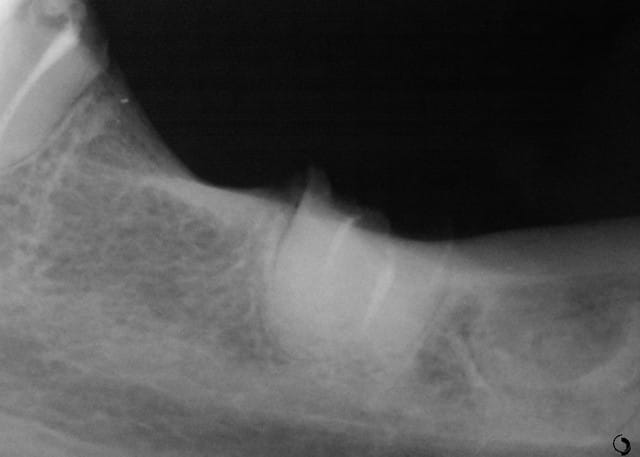

Cette même patiente, pimpante pour ses 90 ans et pleine de gaieté, viens me voir pour son nouvel appareil du bas qu'elle ne supporte pas. Avec surprise, je découvre dessous des chicots abandonnés par son ancien dentiste avec des inflammations gingivales. Radios prises, je lui propose de tenter de les récupérer pour lui réaliser des bridges en remplacement de son appareil, à l'inverse de ce qui se fait habituellement.

La racine résiduelle de la 37 était logée au fond d'un entonnoir gingival au ras de l'os et la 46 était trop délabrée pour la conserver entière. Après quelques séances de gingivoplasties et de tailles, le pari était gagné et les bridges ont pu être scellés, la patiente était radieuse!